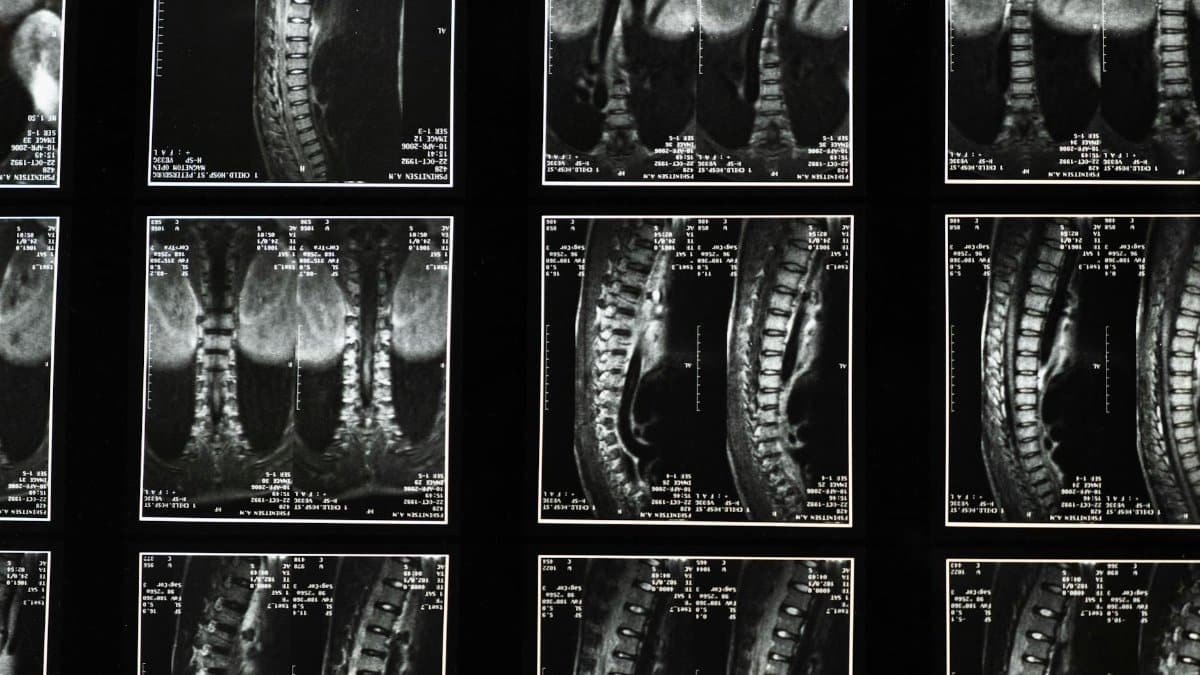

Comprehensive spinal x-ray images, ideal for medical studies and diagnostics.

In the U.S., cervical issues affect millions, with disc replacement gaining traction for its motion-preserving benefits. Pink’s emergency case exemplifies why timely action matters—delays can worsen outcomes. Her hospital stay over New Year’s underscores the procedure’s role in modern medicine, offering relief where conservative treatments fall short. This pink health update serves as a timely reminder in 2026.